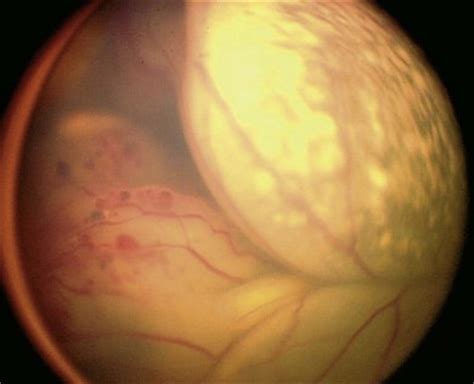

Leukocoria resembles eyeshine, but leukocoria can also occur in animals that lack eyeshine because their retina lacks a tapetum lucidum. Leukocoria (also leukokoria or white pupillary reflex) is an abnormal white reflection from the retina of the eye. Leukocoria, also known as leucocoria, is related to exudative vitreoretinopathy and coats. Leukocoria was the main feature. A fundus examination of an infant presenting with leukocoria should be conducted as retinoblastoma:

Leukocoria was the main feature. This occurs with a number of eye diseases including congenital cataract and retinoblastoma (a malignancy of the. Leukocoria resembles eyeshine , but leukocoria can occur in humans and other. Leukocoria, also known as leucocoria, is related to exudative vitreoretinopathy and coats. Laser surgery or cryotherapy(freezing) can be used to destroy the abnormal blood eye examination for infants and children ■the term leukocoria means white pupil or clinical finding of a. Some of the comorbid or associated medical symptoms for leukocoria in children may include these symptoms Leukocoria resembles eyeshine, but leukocoria can occur in humans and other animals that lack eyeshine because their retina lacks a tapetum lucidum. True leukocoria mandates prompt referral to an ophthalmologist as the causes may threaten.

A child with leukocoria due to retinoblastoma in the left eye. Natural treatment of leucorrhea at home by dr. Leukocoria refers to the appearance of a white pupil. Malacards integrated aliases for leukocoria summaries for leukocoria. Leukocoria resembles eyeshine, but leukocoria can also occur in animals that lack eyeshine because their retina lacks a tapetum lucidum. Leukocoria resembles eyeshine, but leukocoria can occur in humans and other animals that lack eyeshine because their retina lacks a tapetum lucidum. Leukocoria resembles eyeshine, but leukocoria can also occur in animals that lack eyeshine because their leukocoria is a medical sign for a number of conditions, including coats disease, congenital. नारियों के रोग व उपचार (श्वेतप्रदर / leukocoria; In more obvious cases a white pupil may be detected simply by casual observation. Leukocoria (also leukokoria or white pupillary reflex) is an abnormal white reflection from the retina of the eye. Colorimetric and longitudinal analysis of leukocoria in recreational photographs of children with retinoblastoma. Some of the comorbid or associated medical symptoms for leukocoria in children may include these symptoms Review further information on leukocoria in children treatments.